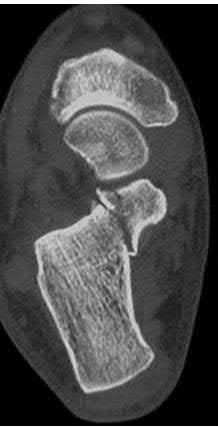

A 64-year-old woman is thrown off a horse, sustaining the injury shown in Figures A and B. She undergoes surgical fixation as seen in Figures C through E. What is the most commonly reported complication of this procedure?

The patient in the scenario has a 2-part proximal humerus fracture treated with a locking plate as seen in Figures A-E. The most common complication with the use of this implant is screw penetration. The terms screw cut out and penetration are often used interchangeably in the literature with cut out appearing more frequently in reports regarding intertrochanteric fractures.

Owsley et al retrospectively reviewed 53 proximal humerus fractures treated with locking plates and the same post-operative protocol. The most common complication was screw cut out or penetration, followed by varus displacement. They concluded that 3 and 4-part fractures in patients over 60 years have a higher incidence of failure.

Agudelo et al retrospectively reviewed 153 patients at a level-one trauma center treated with proximal humerus locking plates, investigating modes of failure for the implant. They determined that varus malreduction (head-shaft angle